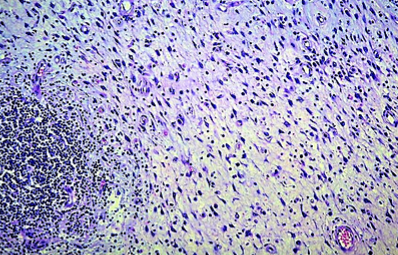

Infiltration of the submucosal layer with granulation tissue (Courtesy Dr. V. Penopoulos)

Preservation of the mucosa is evident, with mildly hypertrophic appearance of the muscularis mucosae (Courtesy Dr. V. Penopoulos)